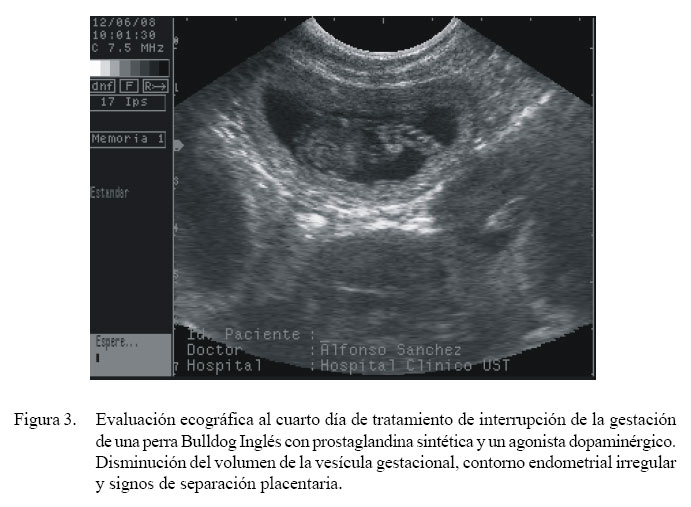

Ecográficamente, se pudo observar cambios en las vesículas gestacionales a partir del día 3 del tratamiento (Fig. 2). En día 4 se intensificaron los cambios morfológicos en las vesículas gestacionales (Fig. 3) y se observó un descenso de la frecuencia cardíaca fetal (<180 lpm). Cinco horas después del tratamiento del día 4 se registró la expulsión de un feto. La hembra fue mantenida en observación sin registrarse más abortos en las horas posteriores. El día siguiente, en el examen ecográfico no se visualizó vesículas gestacionales ni fetos en el útero (Fig. 4).